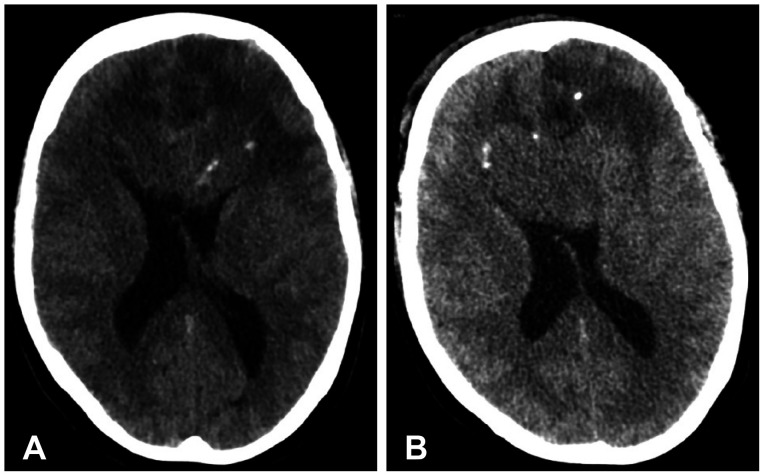

We discuss a patient with a tumor on the anterior corpus callosum who underwent open biopsy eventually succumbing to cerebrogenic fatal arrhythmia following wounded glioma syndrome. A healthy 37-year-old female patient was admitted to our department due to a history of headache for 13 months. MRI revealed a suspicious glioma infiltrating the anterior corpus callosum. Neurologic examination only showed low cognitive assessment score (Montreal Cognitive Assessment score 20/30). ECG was normal sinus rhythm. Steroids and levetiracetam were administered prior to operation. Patient underwent right frontal craniotomy and biopsy of tumor with unremarkable events. During the first hospital day, patient had episodes of bradycardia followed by decrease in sensorium. Brain CT scan showed progression of edema without hemorrhage within the tumor bed. This was followed minutes later by two episodes of generalized tonic-clonic seizures and pulseless ventricular tachycardia. Cardiac resuscitation was done for 24 minutes but patient eventually expired. Location of the lesion and the epileptogenicity of the peritumoral cortex greatly contributed to the patient's demise. Involvement of the fronto-mesial structures, particularly the insula and the cingulate cortex, and their connection to the central autonomic network, increased susceptibility to arrhythmias. Decreased seizure threshold worsened post-operative edema, further aggravating the dysregulation of the brain-heart-connection.